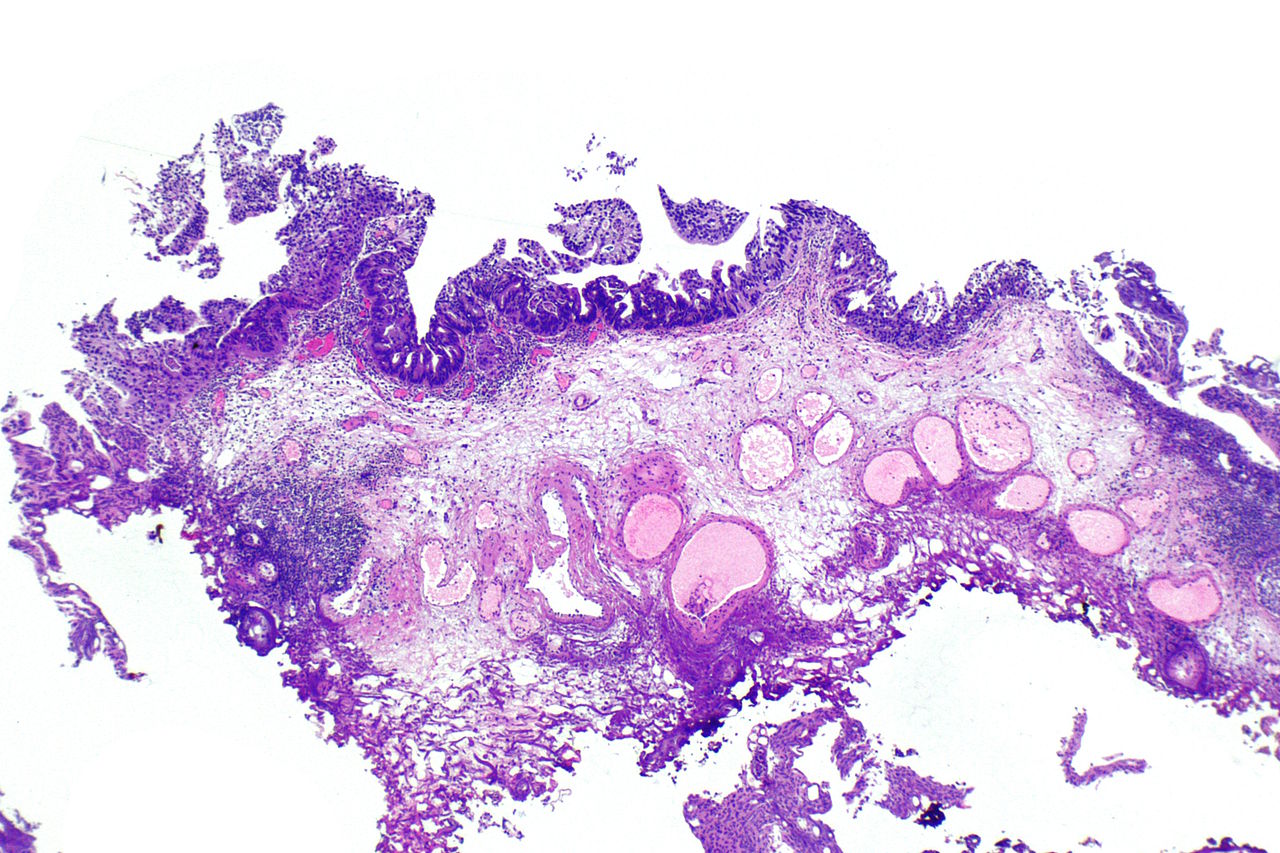

Карнификация Легкого: Микропрепараты и Диагностика

Раздел: Калейдоскоп образов